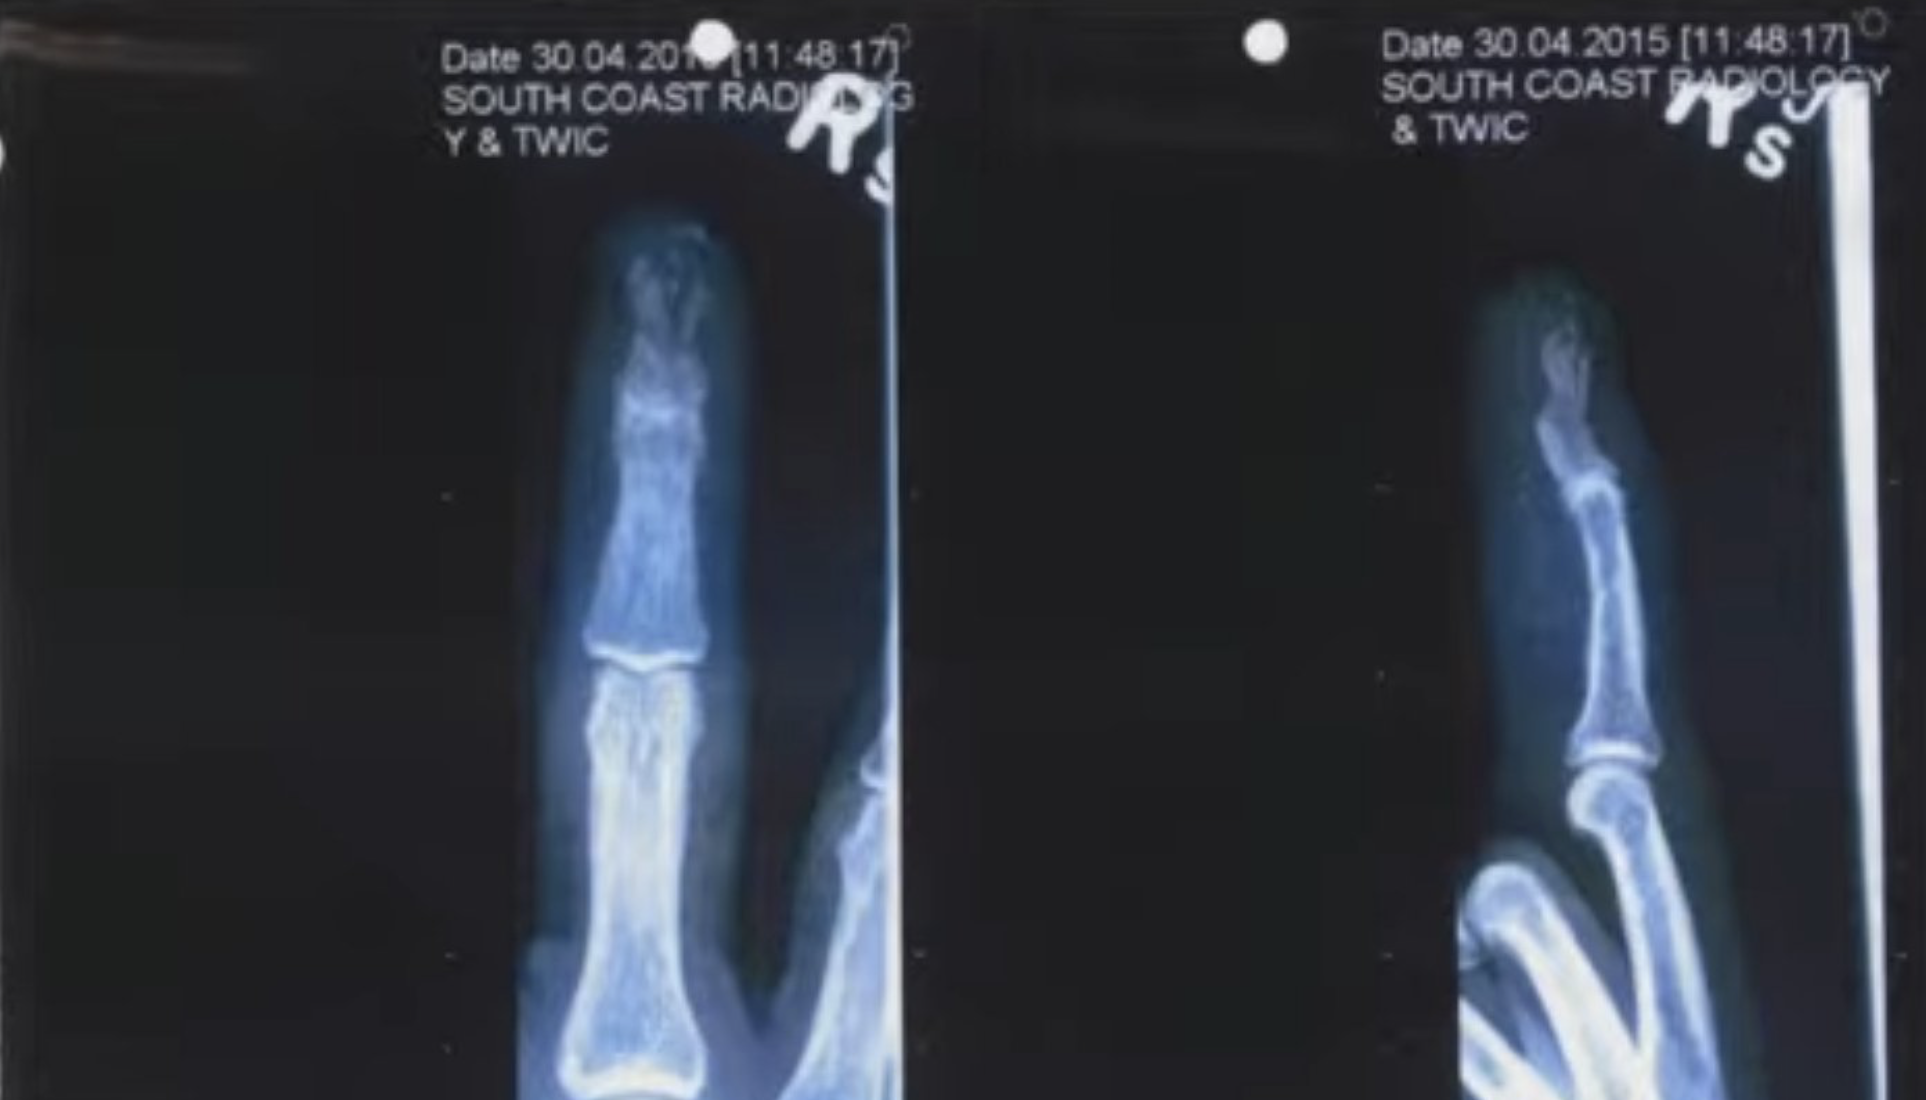

Johnny Depp's Finger Injury.

Over the past month, millions have been watching the Johnny Depp & Amber Heard trial. From a plastic surgery perspective, it was interesting to watch the medicolegal hand surgeon "experts" testify about his injury.

The question each expert had to answer was - how did Johnny Depp actually injure his finger? Was it a self-induced crush injury from a door or was it from a vodka bottle thrown by Amber Heard?

Images from Sky News

Three hand surgeons testified to the jury (except the original surgeon that saw him when the injury occured in Australia). They were asked to confirm if the history correlated with clinical findings.

Let's put yourself in the shoes of these expert hand surgeons. Remember, none of them were the actual original surgeon that treated him. Regardless, they were expected to answer this question - how do you think he injured his finger?